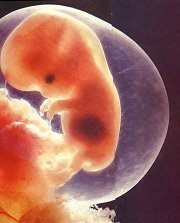

受精後6星期,人形已隱約可見。這時,胚胎的心跳每分鐘140~150下.是母親心跳的兩倍。